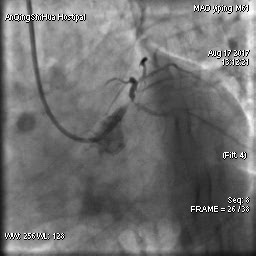

然而,冠狀動脈造影的結(jié)果讓所有人都大吃一驚!

毛先生的血管在心臟左主干體部及分叉部都出現(xiàn)嚴重狹窄,僅一絲血流通過,前降支的血流已明顯減慢。難怪日常步行都會引起心絞痛,毛先生隨時都可能心臟驟停。

術(shù)前 心臟左主干末端嚴重狹窄